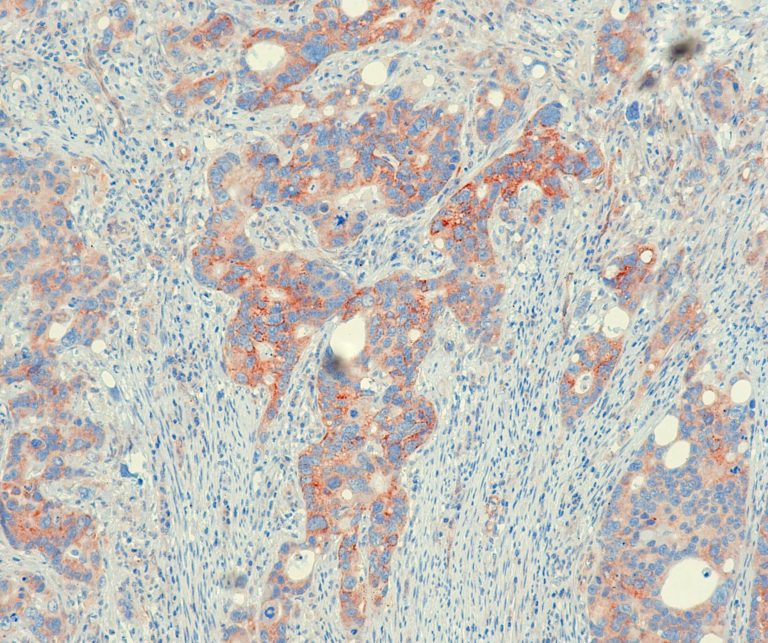

Vascular Pathology

Gastrointestinal (GI) Pathology

General Marker

Breast Pathology

Endocrine Pathology

Gynecological Pathology

Neuropathology

Infection Markers

Lung Pathology

Urinary Tract Pathology

Transplantation Pathology

Soft Tissue Pathology

Hematopathology